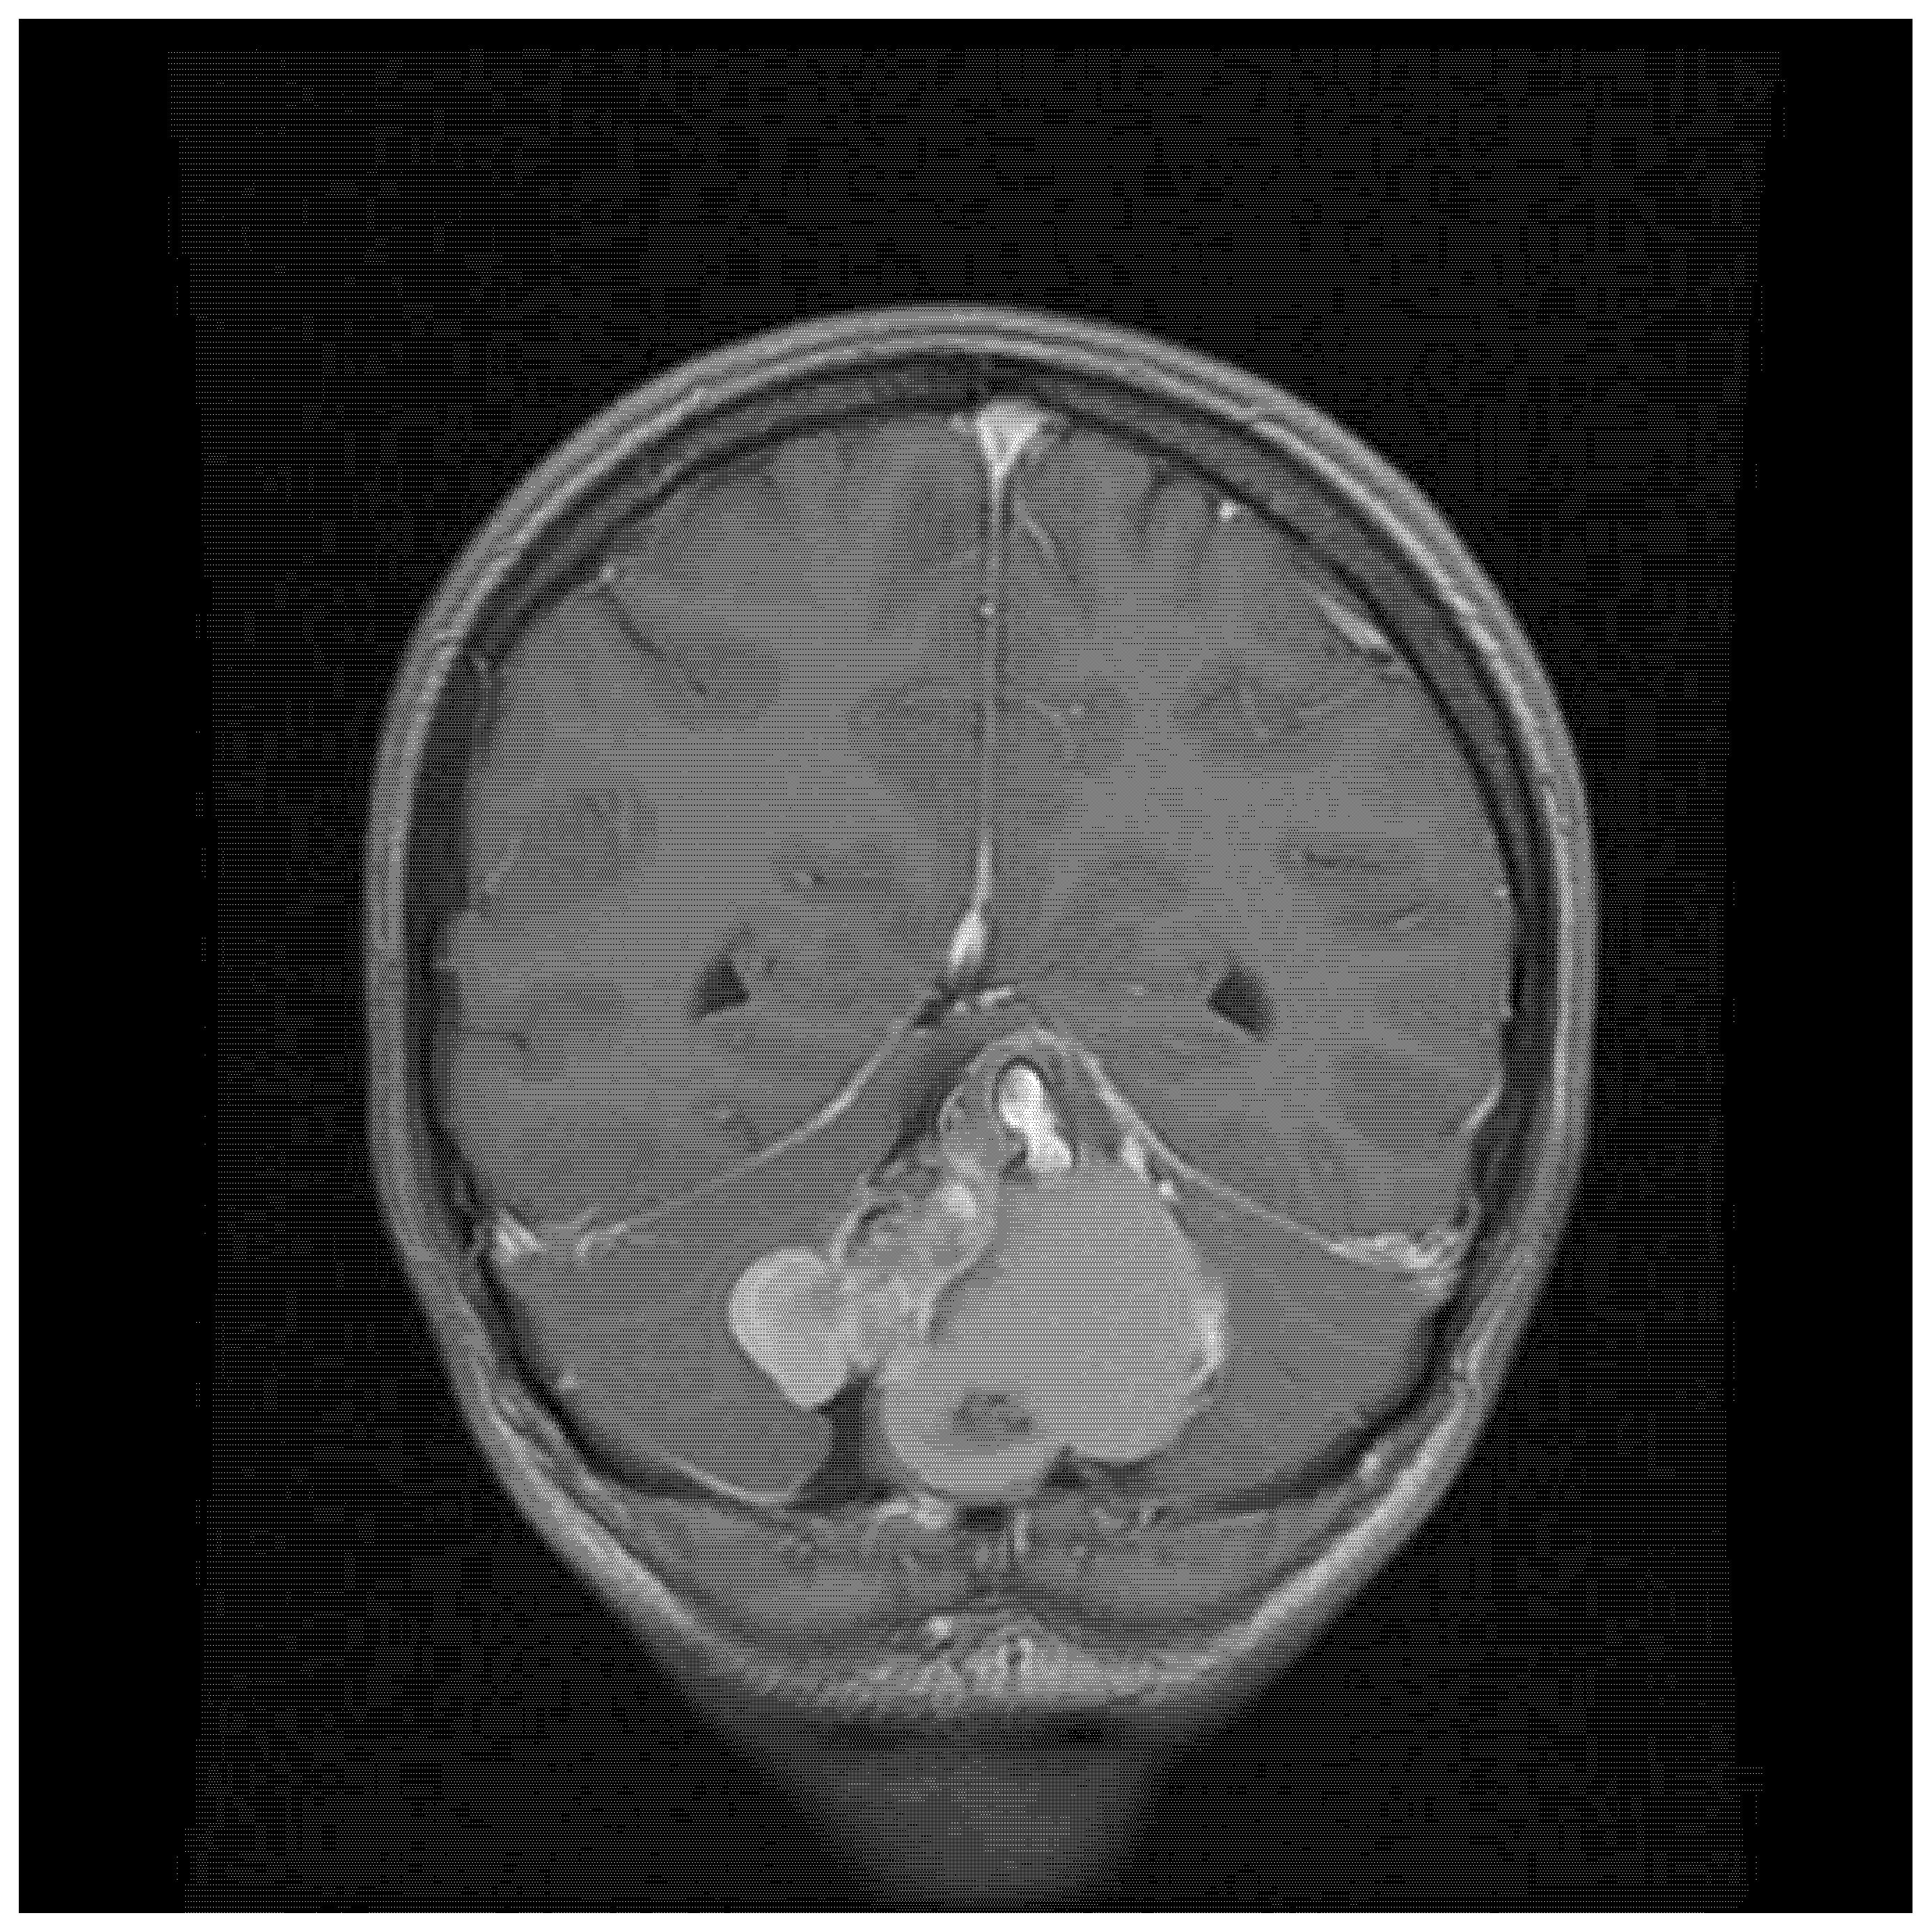

| 22/female | cerebellum—midline | mature teratoma | severe headache | current case |